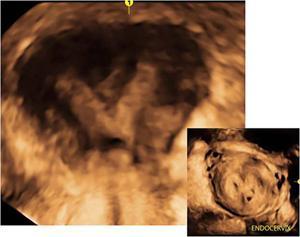

MÜLLERIAN DUCT ANOMALIES Rajani Gorantla Müllerian ducts are a pair of tubular structures that give rise to uterus, cervix, fallopian tubes and upper two-thirds of vagina. Disruption or failure of normal development can result in occurrence of Müllerian duct anomalies (MDAs). These are commonly associated with other congenital anomalies of urinary tract and ovaries due to the close relationship between the development of mesonephric and paramesonephric ducts; few patients also have associated skeletal system anomalies. The prevalence of MDAs in an unselected population was 5.5%; 8% among the infertile women, 12.3% in women with a history of recurrent pregnancy loss and 24.5% in women with miscarriage and infertility. Most of the patients with MDAs are asymptomatic and found incidentally on imaging for any other gynaecological problems, in evaluation of a patient with renal, skeletal or abdominal wall abnormalities. In symptomatic women, complains are related to the type, severity, obstructive anomaly or nonobstructive anomaly. The symptoms can be obstetric or gynaecological related, includes recurrent spontaneous abortions, infertility, preterm labour, intrauterine growth restriction and abnormal foetal lie. Few adolescent girls may present with primary amenorrhoea, hypomenorrhoea, abnormal vaginal bleeding, cyclical pain and mass. Rarely they can present with pelvic inflammatory disease with abnormal vaginal discharge, dyspareunia and urinary tract infections. The female reproductive system develops from a pair of Müllerian or paramesonephric ducts, urogenital sinus and vaginal plate. The ovaries develop separately from the primordial ridge. It is of great importance to understand the normal stages of development, as failure or interruption of any of these stages can lead to a simple to complex spectrum of anomalies. The three stages of Müllerian duct development include: At 6–10 weeks of gestation age, two paired Müllerian ducts and Wolffian ducts formation occurs. When Y chromosome factor (testicular determining factor) is absent, the Wolffian ducts undergo degeneration. The Müllerian ducts further elongate caudally and cross the Wolffian ducts to fuse in the midline. At 10–13 weeks of gestation age, caudal and lateral fusion of the two Müllerian ducts forms primitive uterovaginal canal, which is possessed of solid tissue initially located side by side and further internal canalization leads to the formation of two channels/canals divided by a septum. At this stage, there is reabsorption of the caudal septum and forms single cervical canal and vagina lumen. In around 15–20 weeks of gestation age, complete resorption of the septum takes place in a caudocranial direction from the isthmus to fundus and development of single endometrial cavity results. The fused caudal part of Müllerian ducts gives rise to the uterus, cervix and upper two-thirds of vagina; the unfused cranial part forms the fallopian tubes (Fig. 11.14.1.1). The lower vagina develops from the urogenital sinus, which is separated from the rectum by urorectal septum around 7 weeks of gestation age. The primitive uterovaginal canal embeds into the dorsal wall of urogenital sinus and forms Muller’s tubercle. Around 13 weeks of gestation, two solid masses known as sinovaginal bulbs originate from the upper part of the Muller’s tubercle, further proliferate into the caudal end of the uterovaginal canal to become a solid vaginal plate. Later canalization or degeneration of the central cells of the vaginal plate forms the lower vagina, which is usually completed by 20 weeks’ gestation. The vertical fusion of the upper and lower vagina occurs with resorption of tissue in between and forms single vaginal cavity (Fig. 11.14.1.2). The vaginal lumen is separated from the urogenital sinus by the hymenal membrane. Just before birth, the hymen normally ruptures due to retrogression of the central epithelial cells. However, a thin fold of mucous membrane persists around the vaginal introitus. The ovaries develop separately from migration of primordial germ cells to the genital ridge. Ureteric buds develop separately and concurrently. So renal anomalies are most commonly associated with MDAs with an association of 30%–50%. Various classification systems have been proposed over the past several decades to describe MDAs. Ideally, same classification system needs to be followed by a gynaecologist, surgeon and radiologist for better communication. Buttram and Gibbons classification was suggested in 1979, and it was based upon the level of failure in normal development and segregate the anomalies into groups with similar clinical manifestations, treatment, and prognosis for foetal salvage. According to Buttram and Gibbons, the uterine anomalies were classified into six classes as described in Table 11.14.1.1. The drawback is the lack of classification of vaginal and other anomalies separately. The ASRM (previously the American Fertility Society – AFS) classification system is the most widely accepted classification worldwide over the past years and was introduced in 1988. According to this classification, MDAs are classified into seven classes (class I to class VII) as mentioned in Table 11.14.1.2. However, several limitations have been described by Grimbizis and Campo in 2010 (Fig. 11.14.1.3). The drawbacks of the ASRM classification system are as follows: Hence in 2016, an updated classification of uterine septum, that is ASRM-2016 was proposed and officially approved morphometric criteria are given for distinguishing between septate, normal/arcuate and bicornuate uteri (Table 11.14.1.3). The VCUAM classification was proposed in the year 2005. The main concern is to provide a simple, systematic, clinical classification in addition to providing a precise reflection of the entire malformation. The female genital organs were divided into the following subgroups in accordance with the anatomy: vagina (V), cervix (C), uterus (U) and adnexa (A). Associated malformations were assigned to a subgroup (M) relative to each specific organ. The disadvantage is due to its inherent complexity, and more than 56,700 individual combinations of anomalies are possible. ESHRE and ESGE established a common working group named CONgenital UTerine Anomalies (CONUTA) in order to devise an improved classification system (Table 11.14.1.4). It was published in 2013. Anatomy is the basis for systemic categorization of the MDAs. The subclasses are divided by the different degrees of uterine deformity and their clinical significance (Fig. 11.14.1.4). Cervical and vaginal anomalies are classified into independent supplementary subclasses (Figs. 11.14.1.5–11.14.1.6). For most of the clinicians, it helped as starting point for the development of guidelines for their diagnosis and treatment. The malformations are graded according to severity, U0–U5, C0–C4 and V0–V4, with U5, C4 and V4 being more severe. Class U3 incorporates bicorporeal fusion defects (didelphys and bicornuate) as this was considered as a more functional mode of classification. Arcuate uterus was not included separately, but this is categorized under normal variant into class U1c. Recent studies have demonstrated that the ESHRE/ESGE system provides an effective and comprehensive classification for almost all the currently known MDAs and overcomes the limits of previous classifications. However, there is a relative overdiagnosis of septate uterus with the application of ESHRE–ESGE criteria has been reported and which potentially might lead to unnecessary surgical overtreatment. C0 C1 C2 Normal cervix Septate cervix Double ‘normal’ cervix C3 C4 Unilateral cervical aplasia Cervical aplasia U4 V0 V1 V2 V3 Normal vagina Longitudinal nonobstructing vaginal septum Longitudinal obstructing vaginal septum Transverse vaginal septum and/or imperforate hymen V4 Vaginal aplasia C MDAs’ characterization and classification is of great significance, as the treatment is determined by the type and severity of abnormality. The various imaging modalities available include: HSG was the most recognized imaging modality, earlier to the development of the ultrasonography (USG) and MRI. It is an invasive fluoroscopic-guided procedure for uterine and tubal assessment, and is performed during the midproliferative phase of the cycle, ideally between days 7 and 10 of the cycle when endometrium is thin. Fluoroscopic spot images obtained to evaluate uterine configuration, uterine filling defects and fallopian tube patency. HSG allows evaluation of only the component of the uterine cavity that communicates with the cervix. The anatomic information about myometrium and external fundal contour will not be provided by HSG. The diagnostic criteria used to diagnose MDAs on HSG include: HSG findings of different MDAs are described in Table 11.14.1.5 and Fig. 11.14.1.10. Virtual HSG is a noninvasive technique performed by using a computed tomography (CT) scanner, done 45 s after the contrast material instillation begins. Contraindications are similar to those for HSG and include pregnancy and active pelvic infection. There is no necessity for retraction of the uterus or manipulation of the cervix. The procedure is quick, easy and prophylactic administration of antibiotics is not required. The use of a power injector helps to ensure a steady low pressure of instillation. The procedure is less painful, more comfortable and easily tolerated by patients than conventional HSG. Radiation exposure sometimes requires cervical clamping, which may result in complications such as bleeding and infection. Transabdominal pelvic ultrasound can diagnose uterine anomalies with accuracy rate of 47%. Two-dimensional transvaginal ultrasound (TVUS) has high sensitivity and specificity than transabdominal study and provided some information about external and internal fundal contours. The detection rate is high if the scan is performed in secretory phase due to better visualization of endometrium. Three-dimensional USG shows great accuracy than 2D USG in evaluation of the uterine morphology. The technique of 3D USG varies with different vendors. It displays both the external and internal fundal contours and lower uterine segment by acquisition of single coronal view of uterus (c-view) (Fig. 11.14.1.11). The only disadvantage is that it is transvaginal study and shall not be done in paediatric age group and sexually inactive women. Three-dimensional TVUS has become the first line of screening tool in most of the infertility clinics as it is noninvasive, faster, repeatable, allows storage of volume data and has multiplanar capability for systematic evaluation of the uterine and cervical cavities. The salient features of various Müllerian anomalies on 3D USG are described in Table 11.14.1.6 with images. Three-dimensional ultrasound is combined with sonosalpingography in this technique and provides better delineation of the uterine morphology. It is a less invasive procedure done in proliferative phase with instillation of saline into the uterine cavity and assessment of the uterus will be done. MRI is a universally accepted imaging modality in the documentation of MDAs and accuracy rate of 100% have been reported. MRI provides excellent delineation of both the internal and external uterine anatomies. T2-weighted (T2W) images are the mainstay of pelvic imaging and are performed without fat suppression. T1-weighted (T1W) images are mainly for the haemorrhagic content. The disadvantages of MRI include time-consuming procedure, not cost-effective, large body habitus, pacemakers, recent surgical history and claustrophobia. The current and proposed MRI protocol given by the European Society of Urology (ESUR-MRI protocol) intends a dedicated evaluation of MDAs as mentioned below (Fig. 11.14.1.12): Vaginal anomalies can be accurately diagnosed with the prior administration of the ultrasound gel, to distend vagina (Fig. 11.14.1.13). It will help in better diagnosis of complex vaginal anomalies, like vaginal septations or vaginal duplication. The normal MRI appearance of uterocervical canal and vagina are shown in Fig. 11.14.1.14. Uterine aplasia/hypoplasia/agenesis is class 1 MDA according to ASRM classification and U5 uterine anomaly according to ESHRE classification. It is a formation defect of the paramesonephric ducts with complete or segmental agenesis of uterus and vagina. The incidence rate is around 10%–15% of all MDAs and considered as the most severe form of uterine anomaly. Most of them have complete uterovaginal agenesis with no single completely developed uterine cavity and are associated with Mayer–Rokitansky–Küster–Hauser syndrome (MRKHS). Two types of this syndrome are depicted. The typical form or type A represents the absence or remnants of the uterus, cervix, upper two-thirds of vagina with normal ovaries and fallopian tube (Fig. 11.14.1.15). The atypical form or type B is associated with the abnormalities of the ovaries, fallopian tubes and genitourinary system (Fig. 11.14.1.16). In a few cases (approximately 10%), unilateral or bilateral uterine remnants and with or without endometrial cavity will be seen (Fig. 11.14.1.17). Most of them present with primary amenorrhoea due to complete uterovaginal agenesis and manifest as MRKHS. These patients have normal secondary sexual characteristics due to the preserved normal ovarian function and phenotype. If uterine remnants with functional cavity is present, will present with cyclical pain along with amenorrhoea due to cryptomenorrhoea and haematometra. USG is the first modality for identification of these anomalies, absence of uterus with normal ovaries is diagnostic. But, it is difficult to locate the uterine remnants and cavity due to small acoustic window. MRI is the gold standard and it classifies into uterovaginal agenesis and hypoplasia. If hypoplasia is identified, sagittal and axial sections are taken. These remnants are seen as T2 hypointense tubular structures, located in close relation to ovaries in the adnexa. Once we identify the uterine remnants, it is important to look for the functional endometrial cavity. These will have reduced endometrial and myometrial width. MRI can easily delineate the zonal anatomy due to its high soft tissue contrast resolution. The management of Müllerian agenesis consists of counselling for the patient and her parents. Some patients with MRKHS opt for creation of neovagina for normal sexual life. Various techniques are available. In the presence of a functional Müllerian remnant, regardless of whether it is communicating or not, medical suppression of menses can be initiated and should be followed by laparoscopic removal of the hypoplastic remnant. Unicornuate uterus or hemiuterus is defined as the unilateral uterine development and the contralateral Müllerian duct could be either partially formed or absent. It is a formation defect and the necessity to classify it in a different class than that of uterine agenesis, which is also a formation defect, is due to the existence of a fully developed functional uterine hemicavity. It is considered as class II anomaly according to ASRM classification and class U4 according to ESHRE classification. The frequency rate is around 20% of MDAs. Renal anomalies most often occur in association with unicornuate uterus and usually on the same side of uterine agenesis. Further unicornuate uterus is divided into two subclasses depending on the presence or absence of a functional rudimentary cavity in ESHRE classification: In ASRM classification, unicornuate uterus is divided into four subcategories: Mostly asymptomatic and presence of the noncommunicating uterine remnants will be identified at the time of infertility work up or caesarean section. If a functional cavity is present, the presentation is dysmenorrhoea or haematometra in an adolescent. The common obstetrics-related complications include abnormal foetal lie, intrauterine growth retardation, preterm delivery, placental abnormalities and uterine rupture. Gynaecological complications are ectopic pregnancy and endometriosis due to retrograde menstruation. On imaging, unicornuate uterus is seen as tubular and fusiform or banana-shaped structure at paramedian location, the endometrium is narrow and tapers to the apex with normal myometrial anatomy and reduced uterine volume. The rudimentary cavity or remnants are better depicted on 3D USG (Fig. 11.14.1.18) and MRI. However, MRI is superior to USG due to its high soft tissue resolution. The rudimentary cavity can communicate with main cavity or connected by fibrous band. The nonfunctioning cavity will be seen as T2 hypointense structure with loss of zonal anatomy (Figs 11.14.1.19 and 11.14.1.20), whereas the functioning cavity will show the deformed zonal anatomy (Fig. 11.14.1.21), and its complications like haematometra as T1/T2 hyperintense endometrial collection. Unicornuate uterus without rudimentary cavity does not require any procedure. But in the presence of communicating or noncommunicating rudimentary horn, surgical resection must be considered to prevent complications. Uterine didelphys is a class III MDA based on the ASRM classification and class U3b bicorporeal uterus according to ESHRE classification with an incidence rate of 5% among the uterine anomalies. It is a lateral fusion defect; results from complete failure of the Müllerian duct fusion. Two noncommunicating endometrial cavities with preserved zonal anatomy are seen with separate cervix. According to ESHRE classification, it is defined as external fundal indentation completely dividing the uterine corpus up to the level of external cervical os. It is most commonly associated with longitudinal vaginal septum in around 75% of cases. Some patients may show transverse vaginal septum and these will be obstructive or nonobstructive type. Renal anomalies are also commonly associated with uterine didelphys. Uterine didelphys is usually asymptomatic and diagnosed incidentally on pelvic examination or caesarean section. The uterine didelphys with obstructed vagina (Fig. 11.14.1.22) will present at adolescence as dysmenorrhoea, haematometrocolpos and haematosalpinx. Sometimes retrograde menstrual flow can cause endometriosis and pelvic adhesions. Obstetric-related complications include abortion/foetal growth restriction and poor pregnancy outcome. The uterine didelphys with obstructed hemivagina due to transverse vaginal septum and associated ipsilateral renal agenesis are the manifestations of the syndrome called obstructed hemivagina and ipsilateral renal agenesis anomaly/Herlyn–Werner–Wunderlich (HWW) syndrome (Fig. 11.14.1.23).